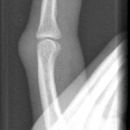

Grundgliedköpfchenfraktur